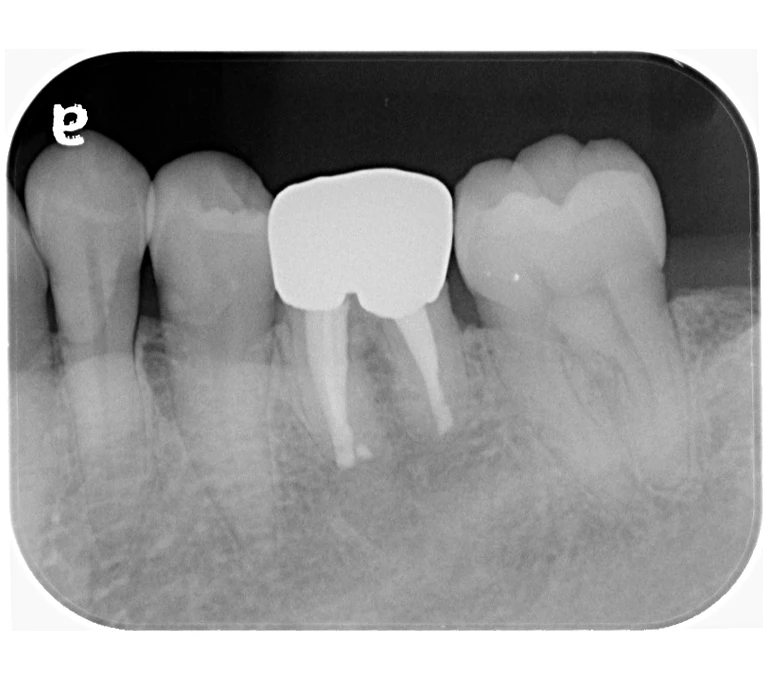

case 2.

治療前

治療後

| 主訴 | 左下歯ぐきの腫れ。 |

|---|---|

| 治療期間 | 約2か月 |

| 治療費 | 約1万5千円 |

| 治療内容 | ラバーダム、マイクロスコープ下にて根管治療を施術。 歯ぐきの腫れ、痛みや違和感が消失したため根管充填、支台築造(土台の製作)を行った。治療後の写真は矯正治療を行うことになったため仮歯を装着した状態。 |

| 治療のリスク | マイクロスコープやCTを使用し、可能な限り精密な根管治療を行っていますが、歯根の形態や病変の大きさ、過去の治療履歴などにより、治癒が得られない場合があります。また、治療後に再感染や歯根破折が生じることもあり、その場合は再治療や抜歯が必要となることがあります。 治療結果には個人差があり、すべての症例で同様の経過を保証するものではありません。 |